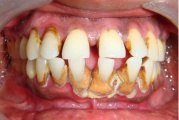

Krooniline parodontiit

Krooniline parodontiit on mikroobide poolt põhjustatud hammaste tugikudede põletik, mille tulemusena tekib progresseeruv alveolaarluu (nähtav röntgenograamil) ja periodontaalligamendi destruktsioon, igemetaskute moodustumine, igeme retsessioon või mõlemad kahjustused kombineeritult. Loe edasi »

- igemed veritsevad (19)

- igemed punetavad (21)

- ige on paistes (mädapunn)

- igemed on tursunud/vohavad (17)

- igemepealne hambakivi (5)

- igemealune hambakivi (4)